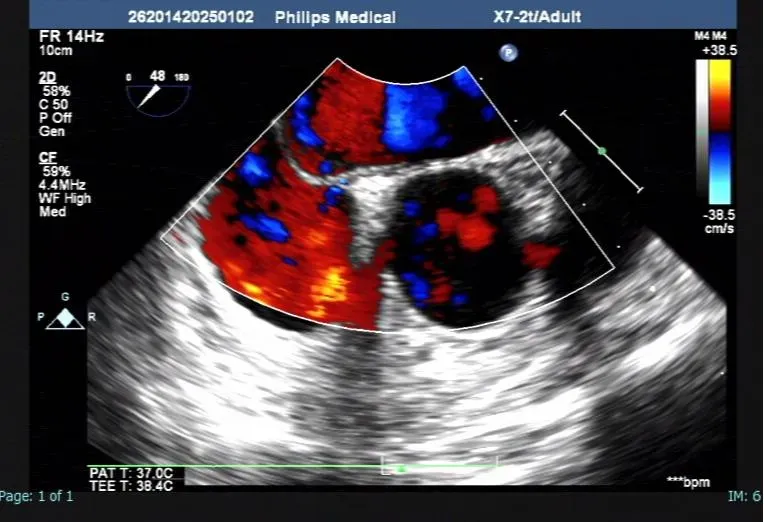

經(jīng)食道超聲可見卵圓孔過隔分流